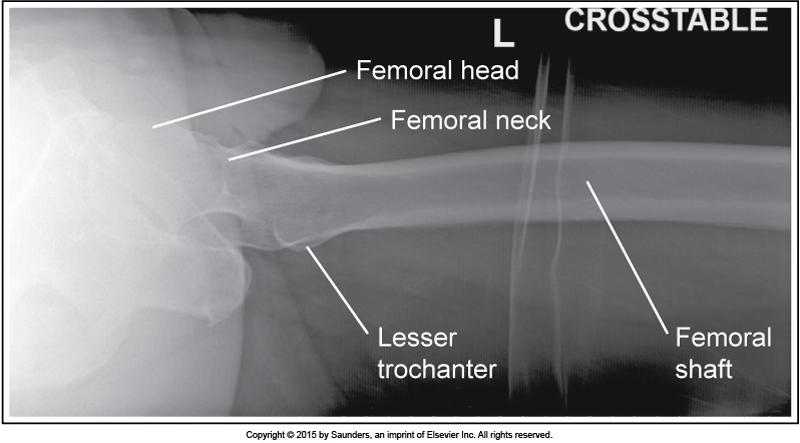

lateral femur

accurate positioning